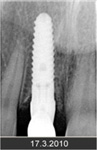

• Zavedení implantátu do kosti čelisti

• Zahojení do kosti – 3-4měsíce(v některých případech i déle – doplňování kosti)